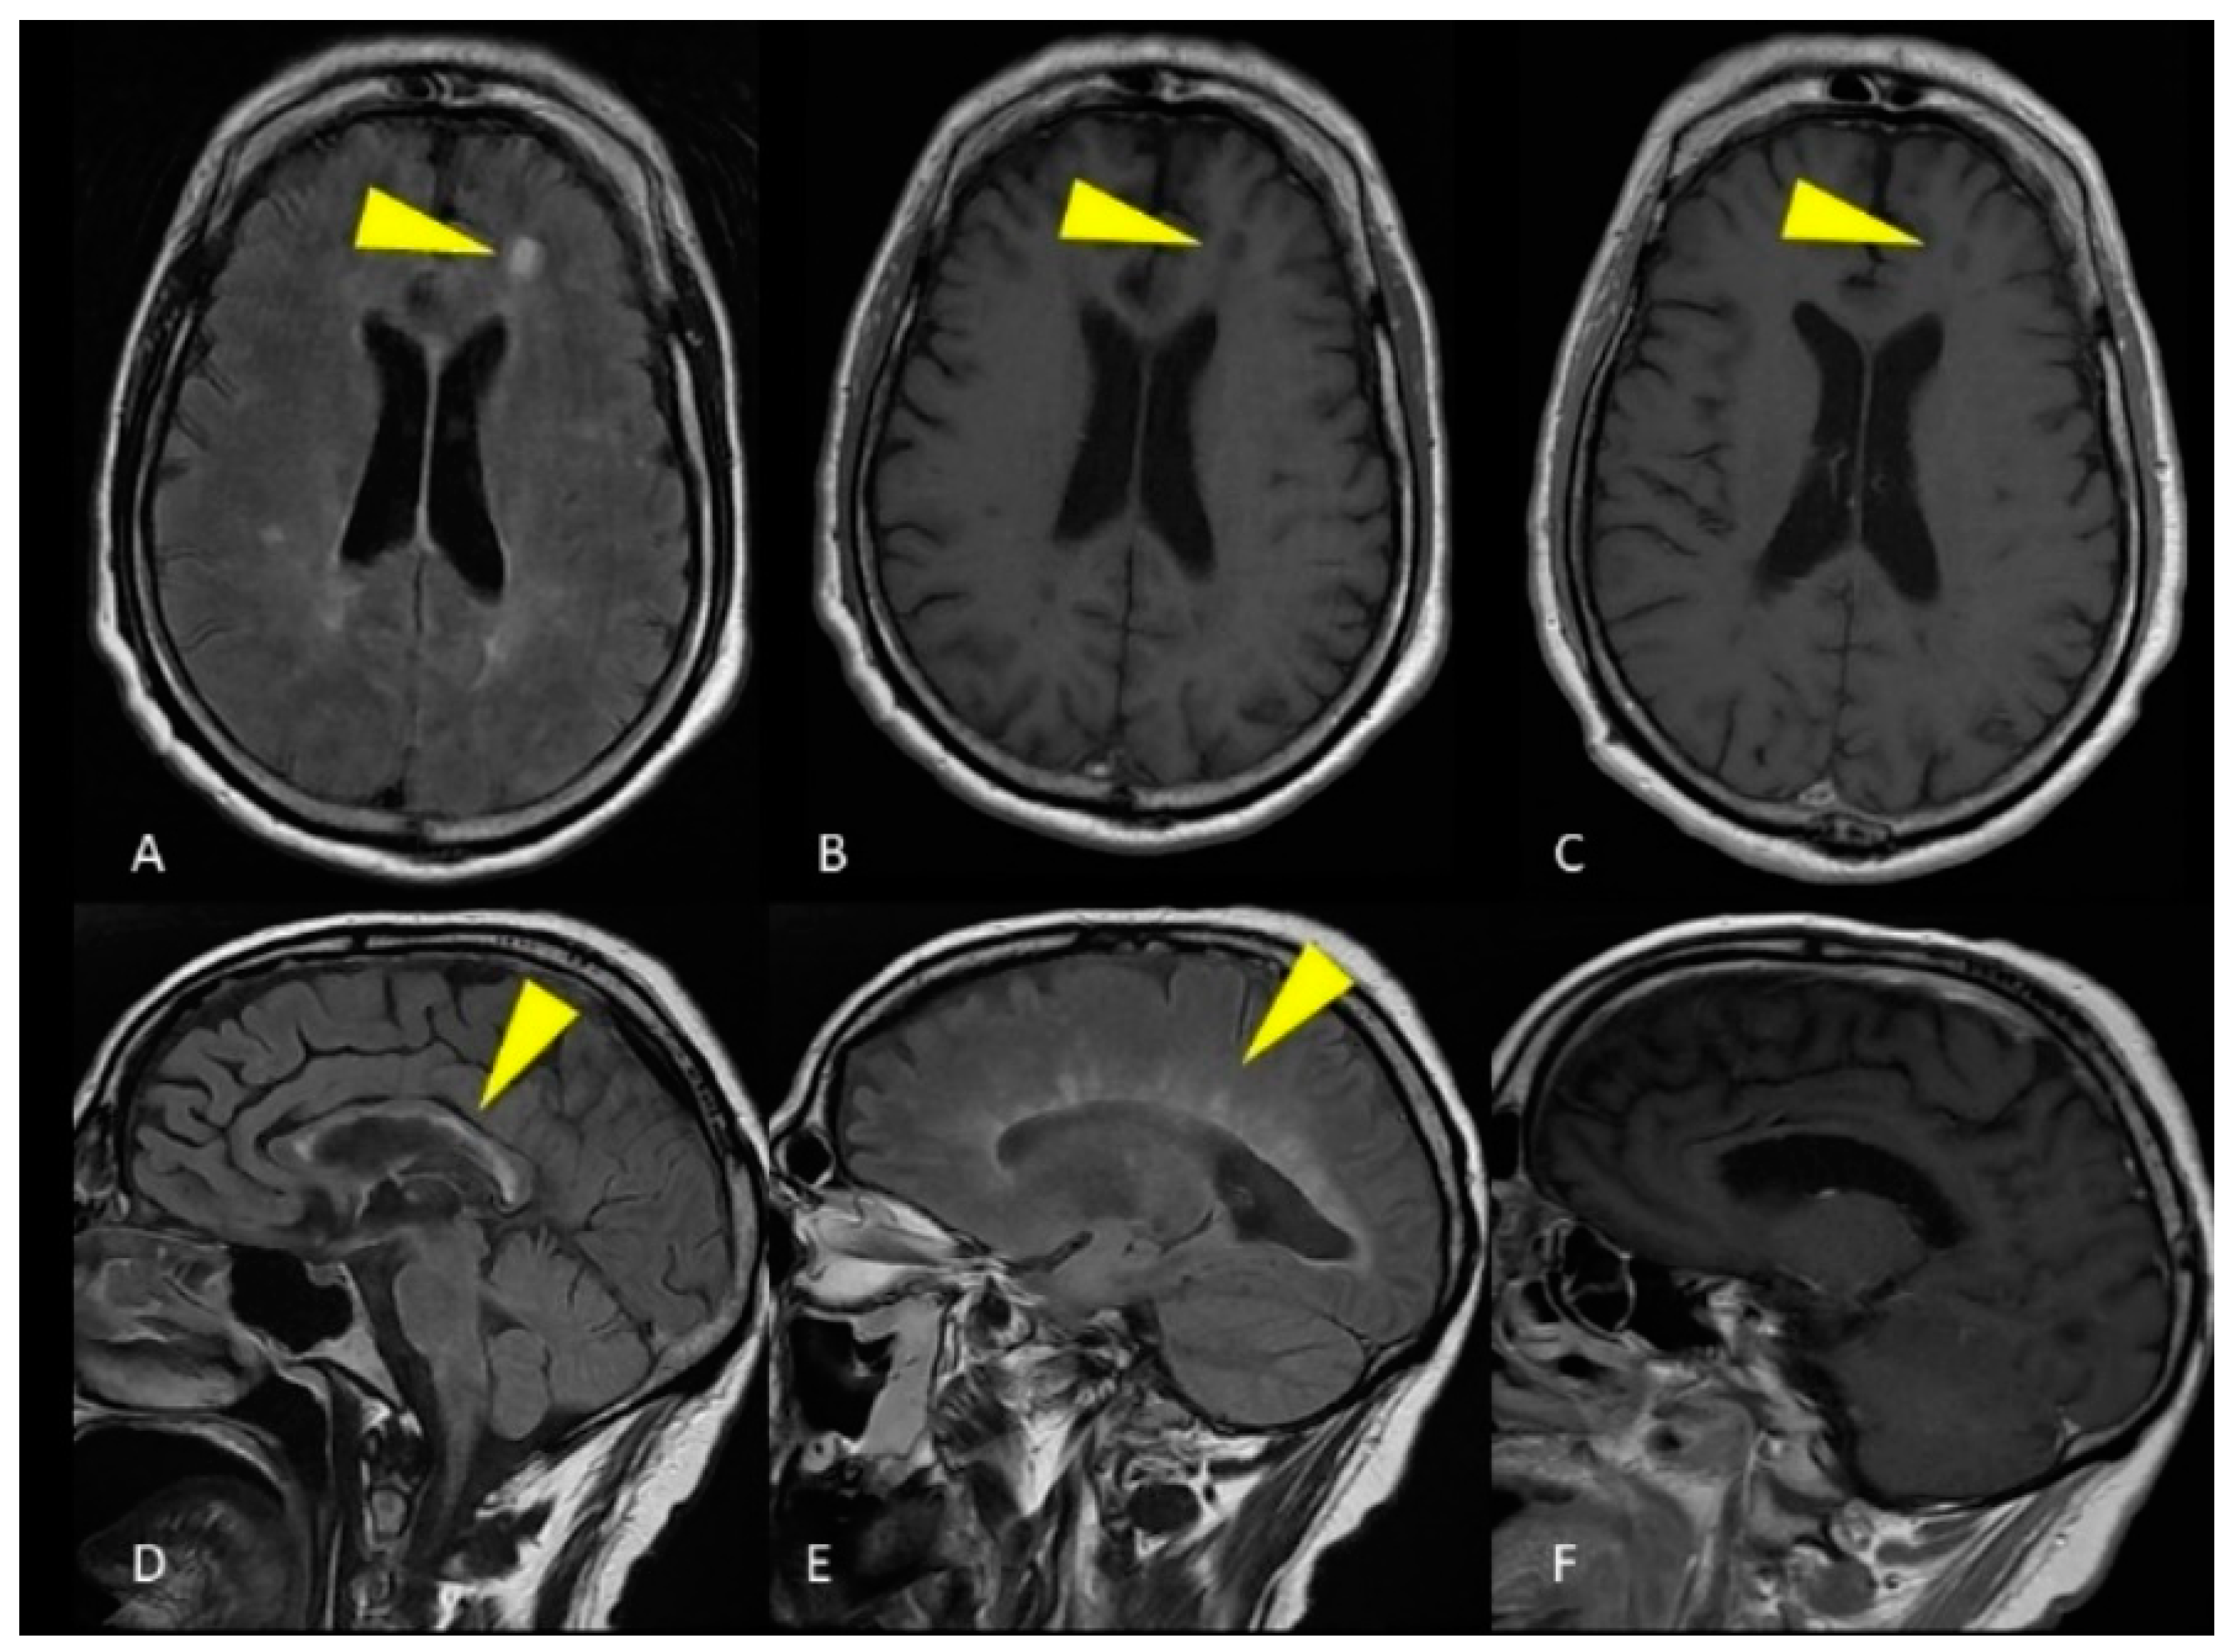

2.1. Case Presentation 1

2.2. Case Presentation 2